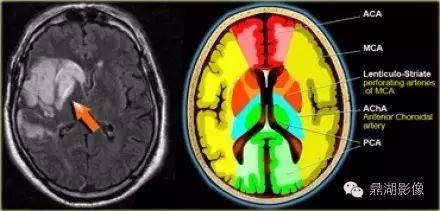

红色ACA:大脑前动脉

黄色MCA:大脑中动脉

绿色PCA:大脑后动脉

蓝色PICA:小脑后下动脉

紫色AICA:小脑前下动脉

灰色SCA:小脑上动脉

浅蓝Branches from Vertebral arteries:椎动脉分支

墨绿Branches from Basilar artery:基底动脉分支

天蓝ACHA:脉络膜前动脉

橙色LSA:豆纹动脉

脉络膜前动脉梗塞

脉络膜前动脉由颈内动脉发出,供应海马,内囊后肢及其外侧

d4a074e938e451b8a6672cf3a2243eaa.jpg

大脑中动脉梗塞(同时累及深穿支及皮层支)